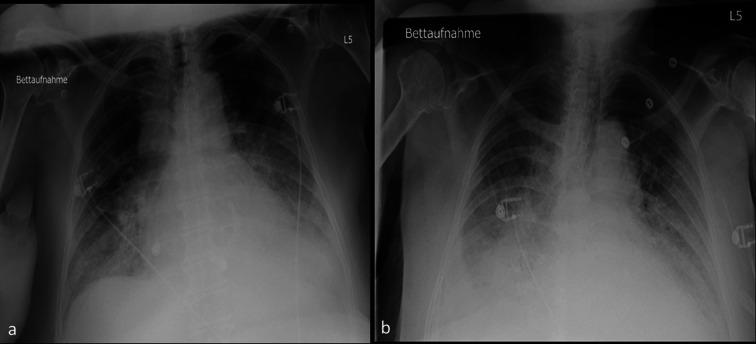

An 82-year-old woman with severe aortic valve stenosis (AS) and a significant proximal right coronary artery (RCA) stenosis presented with decompensated heart failure and acute kidney injury. She was treated with intravascular ultrasound (IVUS)-guided percutaneous coronary intervention (PCI) and trans-oesophageal echocardiography (TOE)-guided transcatheter aortic valve replacement (TAVR).

一名82岁女性,患有严重主动脉瓣狭窄(AS)且右冠状动脉(RCA)近端存在明显狭窄,出现失代偿性心力衰竭和急性肾损伤。她接受了血管内超声(IVUS)引导下的经皮冠状动脉介入治疗(PCI)以及经食管超声心动图(TOE)引导下的经导管主动脉瓣置换术(TAVR)。